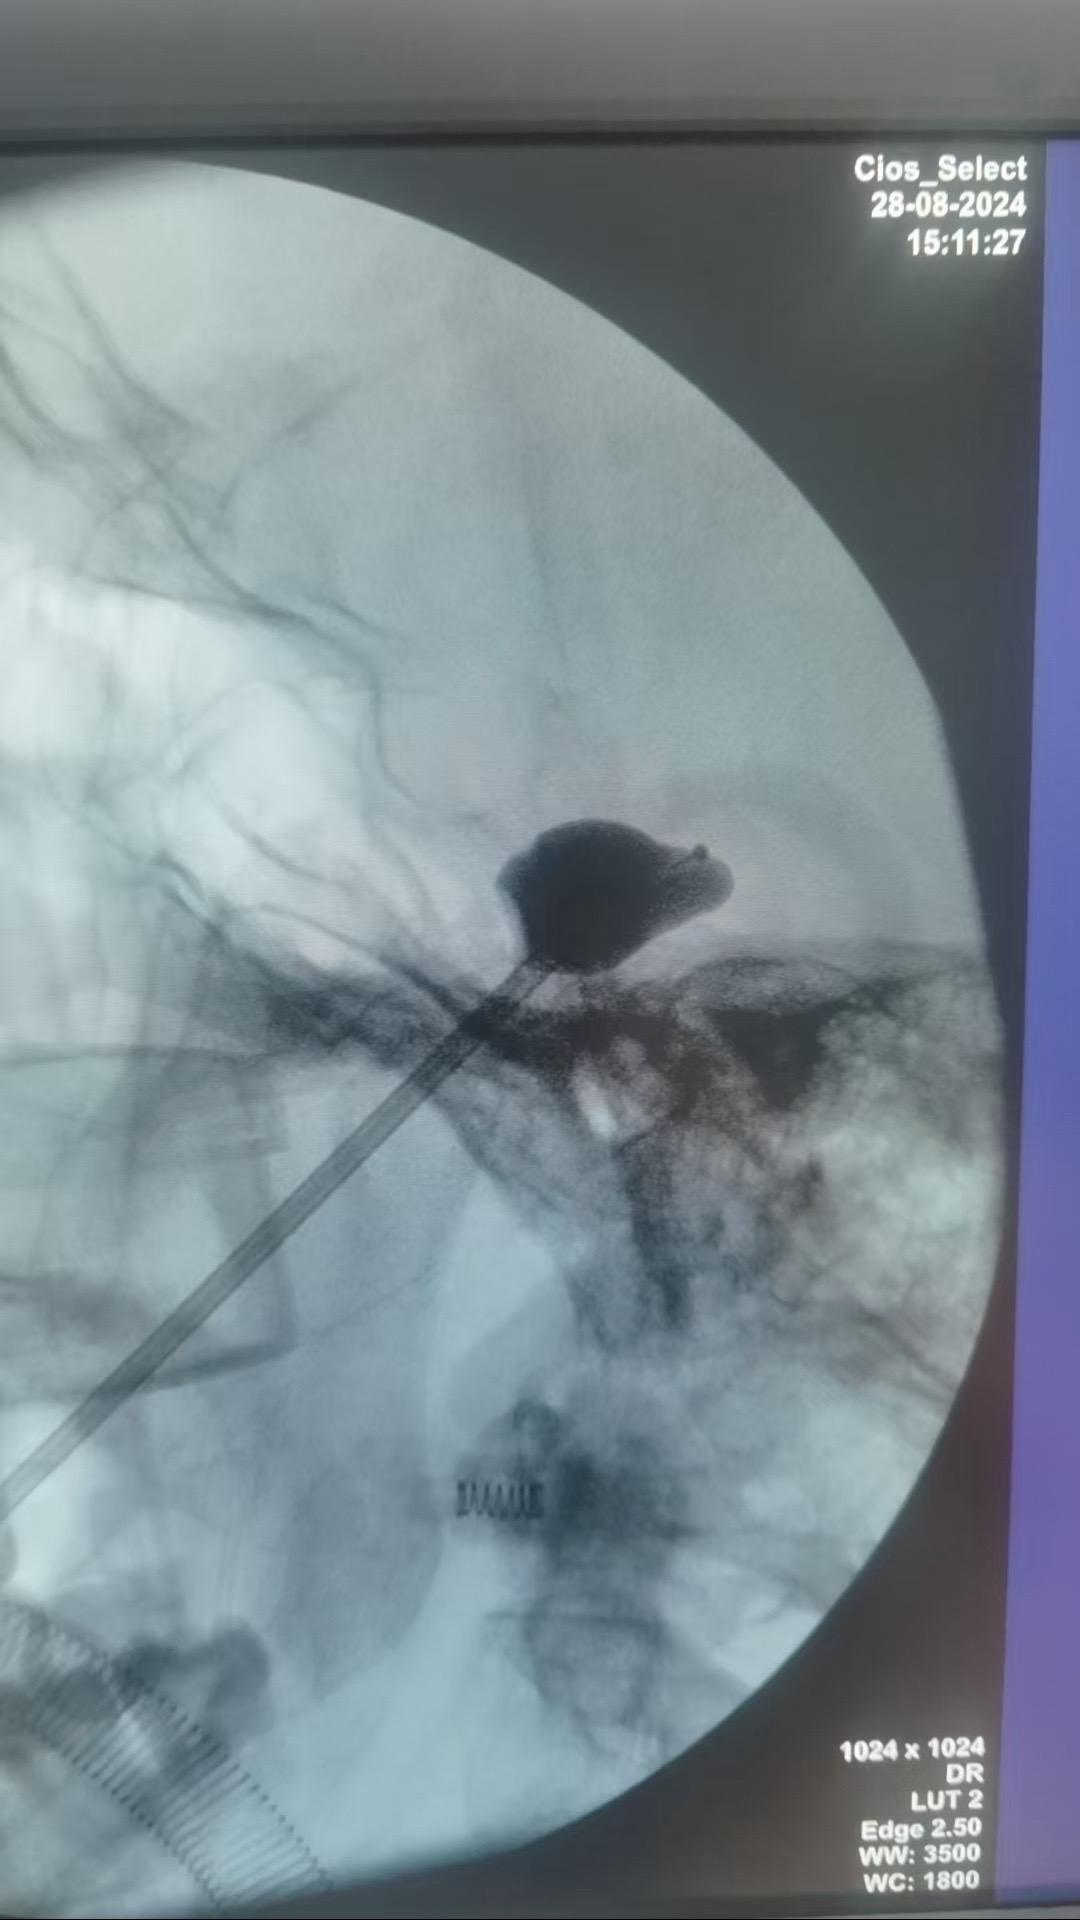

天下武功,唯快不破。针对复发或者不适合手术的天下第一痛---三叉神经痛...